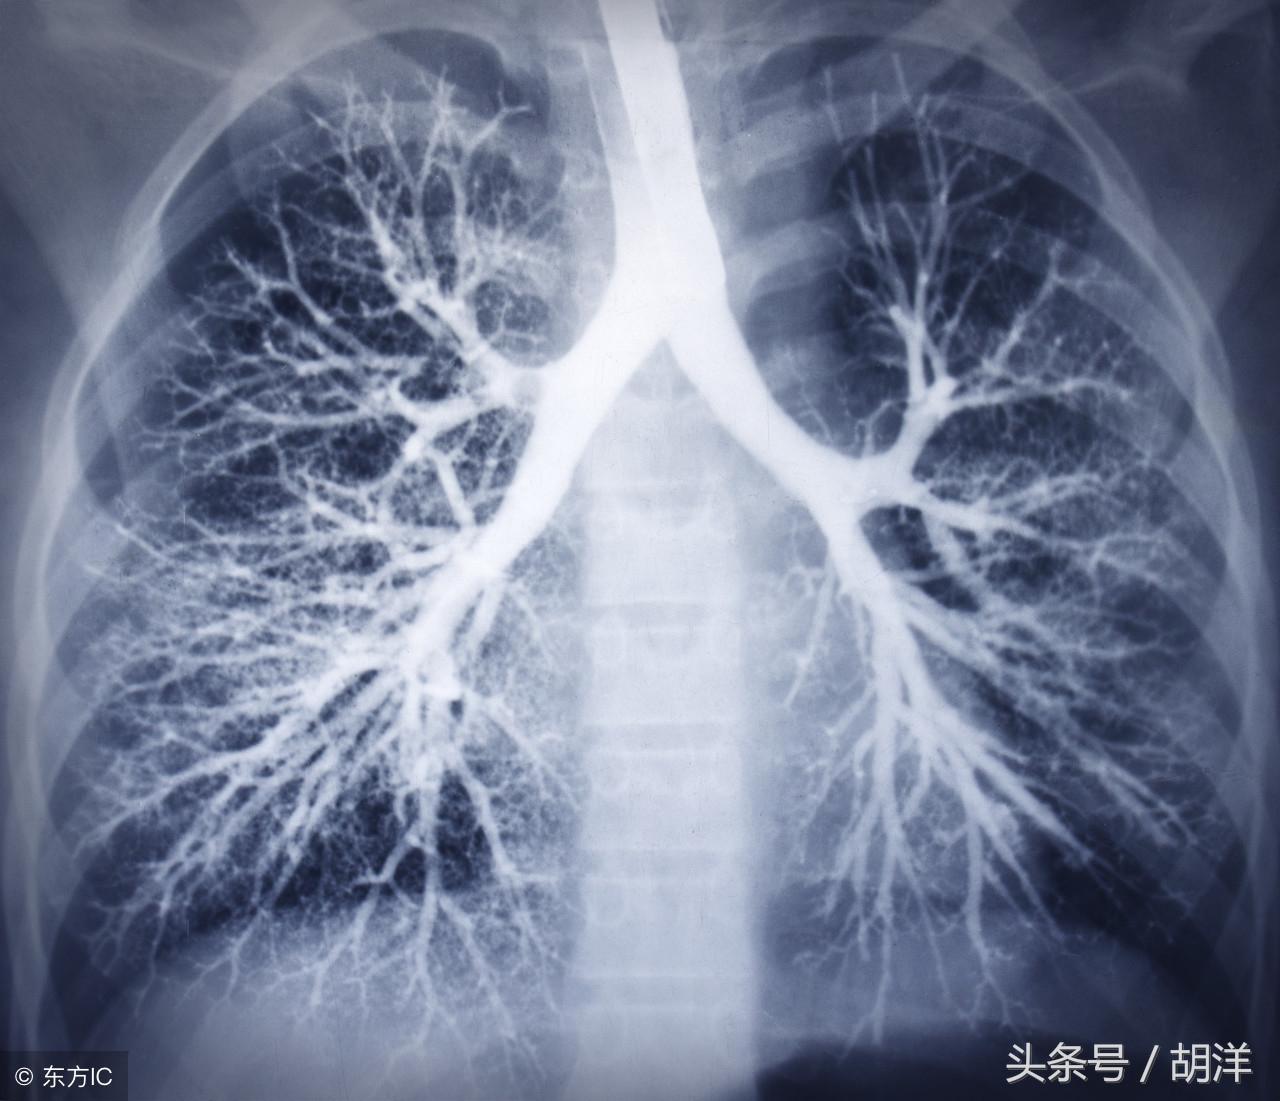

支气管扩张是一种支气管管壁结构破坏性疾病,正常情况下,支气管是一个带有弹性,拥有一定管径的能够维持正常呼吸通气的结构,当管壁结构受到破坏时,气管会受到被动的牵拉而扩张,管壁的血管由于弹性较小,容易被撕扯呈血管瘤改变,一旦胸腔内血流压力增大可能冲破血管瘤变薄的管壁而导致大咯血,少量渗血时则呈现为痰中带血。

曲霉菌是一种常见的真菌,正常情况下,曲菌很少感染肺部结构正常,免疫力良好的人群,当肺部受到破坏,特别是形成较大空洞和支气管扩张时,曲霉菌可以趁机进入空洞扩张的支气管内与其中渗出的白细胞、纤维素等成分形成球状结构,成为曲菌球,曲菌球在空洞内能够自由的活动,对空洞壁有机械性的损伤,当损伤到管壁变异的血管瘤时,极有可能导致大出血。